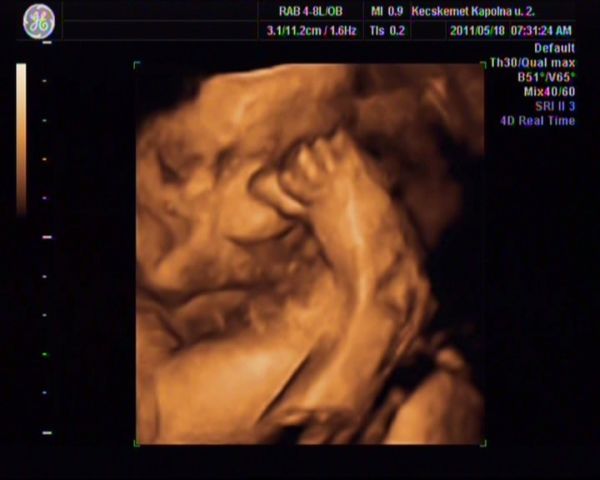

Szépek a pocakok!